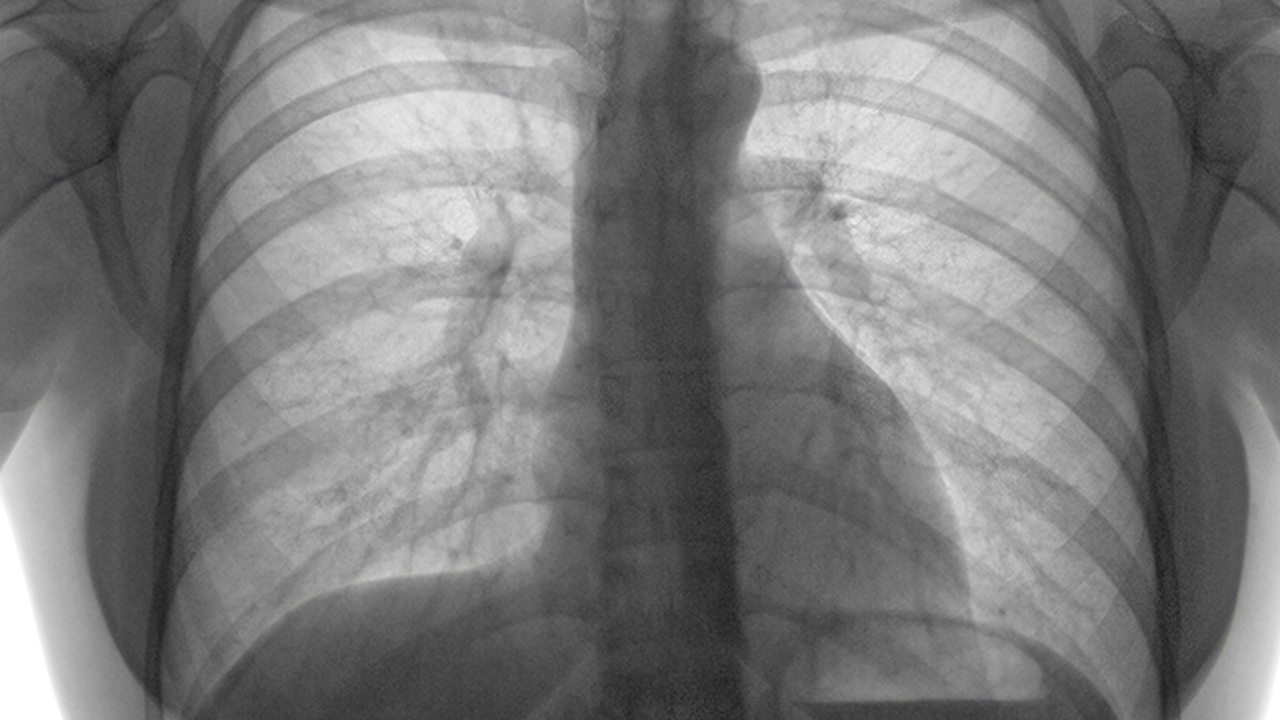

肺癌作为高发恶性肿瘤,其治疗需要多学科协作,涉及手术、放疗、化疗、靶向治疗及免疫治疗等多种手段。南京作为医疗资源丰富的城市,多家三甲医院在肺癌诊疗领域具备较高水平,可为患者提供规范化、个体化的治疗方案。

肺癌的预防与健康管理至关重要。长期吸烟、空气污染、职业暴露(如石棉、放射性物质)是肺癌的主要危险因素。建议高危人群定期进行低剂量螺旋CT筛查,以便早期发现病变。此外,保持健康的生活方式,如戒烟、均衡饮食、适度运动,有助于降低肺癌风险。对于已确诊的患者,应积极配合医生治疗,并定期随访,监测病情变化。